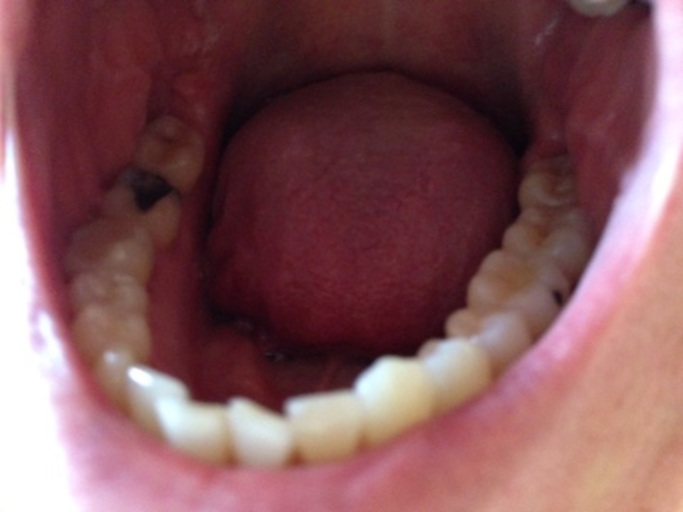

Is this a cavity in my wisdom tooth?

Hi, I am 31 and have observed a dark spot on my lower wisdom tooth (the tooth behind the one with the large silver filling on the picture). All my wisdom teeth have erupted quite good, but short after eruption I had small cavities which were filled with white fillings - that was about 12 years back. Now I see this dark spot which I think might be a new cavity besides the old filling or maybe the old white filling has fallen out. I have no pain from the tooth. I take good care of my teeth and have not had any new cavities for more than 10 years, but I have several fillings from my teenage years and some of those have been refilled over the last five year. Is it a new cavity? Will it be possible to repair my wisdom tooth with a new filling?

It is possible that your resin restoration is stained or may have come out and the underlying tooth structure, dentin, is a darker shade than the harder enamel covering the surface.  Continue with good oral hygiene habits, brushing twice daily and flossing at least once.  Limit high sugar and sticky foods until you see your dentist.  It is best to be proactive and take care of a small cavity when it is diagnosed.  Not only is the procedure less involved, but is usually less costly as well.  Resin restorations usually last 5-10 years, so it may be time to have it replaced.